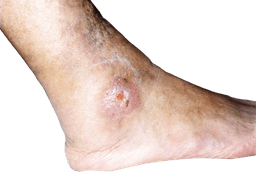

Bensår

Bensår är kroniska, svårläkta sår på underbenen som oftast orsakas av dålig blodcirkulation. Kan vara venösa, arteriella och blandade.